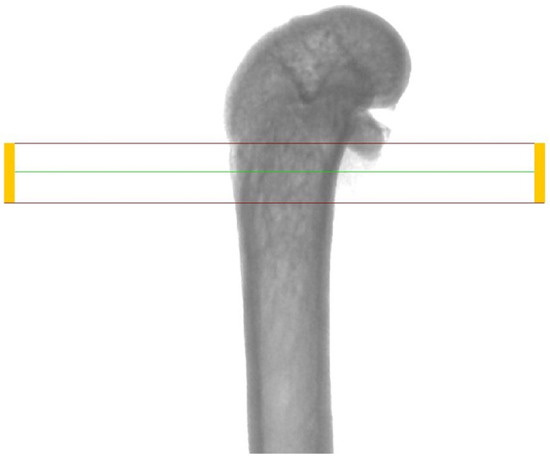

In order to evaluate the microarchitecture of bone tissue, the area of the distal metaphysis of the left femurs of all animals was subjected to microtomographic examination. After defrosting, the samples were placed on a centric stand in the center of the field of view of the microtomography chamber (Skyscan 1072, SkyScan, Antwerp, Belgium) and scanned (magnification 34×, Pixel 8.42, Rotation step 0.23, Exposure 1.9sec, and Gain 1). All of the samples were meticulously positioned so the mid-shaft of the bones was vertically straight and the orientation of the bones was consistent. Raw scans were reconstructed using the nRecon program (Skyscan, Belgium) and then thoroughly analyzed using the Ctan program (Skyscan, Belgium). An identical ROI (region of interest) was subjected to detailed morphometric evaluation. For the trabecular bone in all samples, a 100-slice cylinder was set in the central part of the distal epiphysis at a visual distance from the cortical bone, at the height of 85% of the bone length (Figure 1 and Figure 2). The analysis started at the most proximal end of the distal growth plate, which was visually identified in subsequent sections and taken as the reference point. In the ROI of each tested sample, the following microarchitectonic parameters were analyzed: percent of bone volume (BV/TV), trabecular thickness (Tb.Th), trabecular number (Tb.N), and trabecular separation (Tb.Sp). The surface of the cortical bone was assessed by subtracting the area whose outer border was the cortex’s inner circumference from the femur’s total surface at the level of the most proximal scan of the ROI from each group. Length measurements were measured from the left femur using a caliper. Representative micro-CT overview images are shown in Figure 3, Figure 4 and Figure 5.

Figure 4.

Representative overview photos for group strontium chloride. The picture was taken during the micro-CT analysis (DataViewer SKYSCAN).